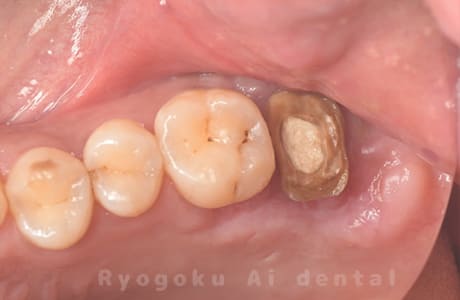

- 原因

- 左上6番重度カリエス

- 治療内容

- クラウンレングスニング

- 治療費用

- 44,000円(根管治療、補綴は別途費用)

他院で抜歯と判断された歯です。クラウンレングスニングを行い、保存を試みました。現在も問題なく被せ物が入り、使用できてます。

<リスク・副作用>

手術後は痛み、腫れ、痺れ、青あざなどの副作用が生じます。痛みは痛み止めを処方しますが、腫れ、青あざは1週間程度生じる場合があります。また、部位によっては神経の走行が複雑で、痺れが残り、長期的にお薬を処方する場合があります。